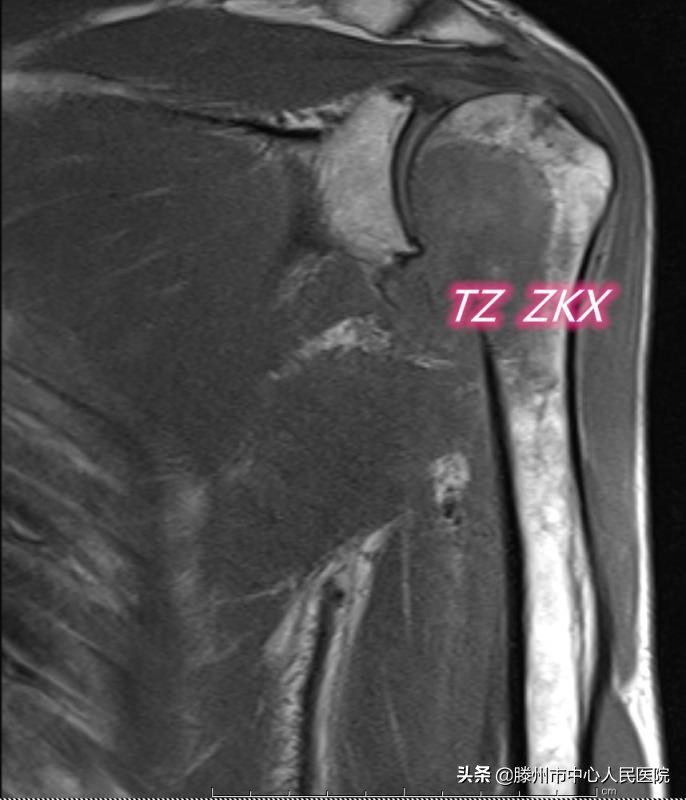

患者71歲,2019年12月診斷胃底-賁門癌并縱膈、腹膜后淋巴結(jié)多發(fā)性轉(zhuǎn)移,經(jīng)過(guò)6個(gè)周期藥物治療,病情穩(wěn)定。3月前出現(xiàn)左側(cè)肩胛部疼痛,逐漸加重,上肢活動(dòng)受限,CT及MRI顯示左側(cè)肱骨頭及肱骨上段溶骨性轉(zhuǎn)移,骨皮質(zhì)破壞范圍超過(guò)1/2,隨時(shí)都有發(fā)生病理性骨折的可能,一旦發(fā)生病理性骨折,必將嚴(yán)重影響患者的生活質(zhì)量。骨科會(huì)診考慮患者高齡,伴有其他多部位轉(zhuǎn)移,不適合手術(shù)治療,建議微創(chuàng)治療。張開賢主任醫(yī)師團(tuán)隊(duì)在借鑒既往多年骨轉(zhuǎn)移瘤微創(chuàng)治療經(jīng)驗(yàn)的基礎(chǔ)上,經(jīng)過(guò)多次討論,決定實(shí)施CT引導(dǎo)微波消融聯(lián)合介入內(nèi)固定及骨水泥成形術(shù)。